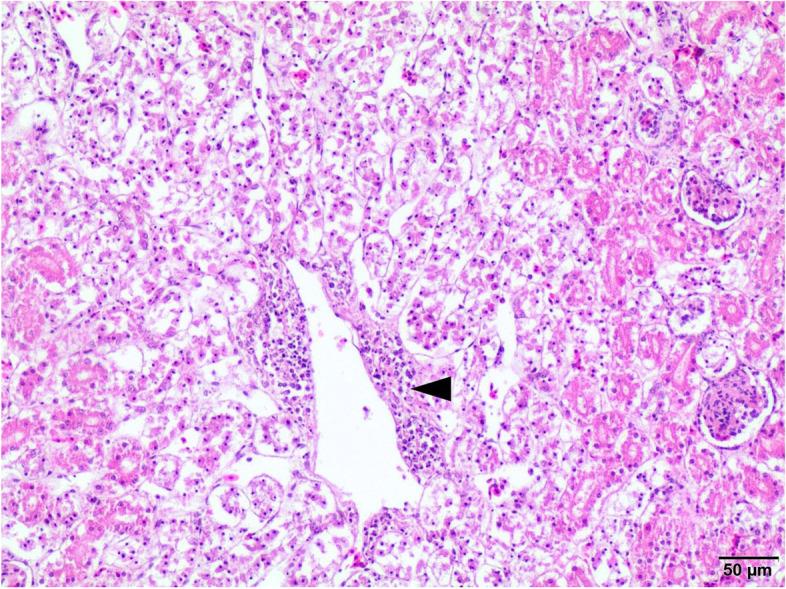

这只 4 岁的孔雀表现为慢性腹泻、消瘦和虚弱。剖检发现肾脏肿大且苍白、小肠黏膜坏死和肠壁增厚,以及心包积液。组织病理学检查显示伴有裂殖体的坏死性肠炎,有明显的单核细胞浸润,此外肝脏和肾脏有败血症的组织学证据。细菌鉴定基于小肠样本的光镜检查、培养和生化试验。进一步的鉴定基于 PCR。通过测定来自 5 个不同类别的 6 种抗菌药物的最小抑菌浓度(MIC)值来确定抗菌药物敏感性谱。PCR 检测用于检测与运动、细胞致死性扩张毒素产生、黏附和内化相关的毒力因子基因。小肠样本的细菌学显示几乎仅存在大量空肠弯曲菌的生长,对环丙沙星、庆大霉素和氨苄西林耐药。细菌对阿莫西林+克拉维酸、四环素和红霉素敏感。所有测试的毒力因子基因均被检出。寄生虫学检查通过新鲜粪便和肠内容物的显微镜检查进行,发现有中等数量的孔雀艾美耳球虫、火鸡组织滴虫、单个毛细线虫卵以及异刺线虫样寄生虫。

上述病例表明,强毒力空肠弯曲菌与寄生虫侵袭的组合可能导致孔雀慢性肠炎,这很可能导致宿主极度衰竭和死亡。